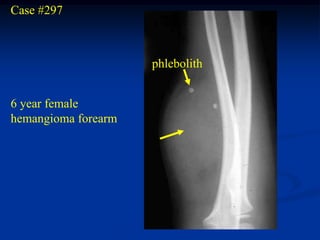

Case #297

phlebolith

6 year female

hemangioma forearm

Case #297 phlebolith 6 year female hemangioma forearm

• 307.